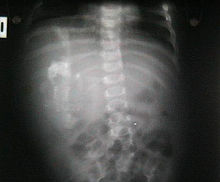

Anteroposterior abdominal radiograph shows a soft-tissue mass in the right hemiabdomen. The mass contains calcified osseous-appearing structures of varying sizes and shapes.